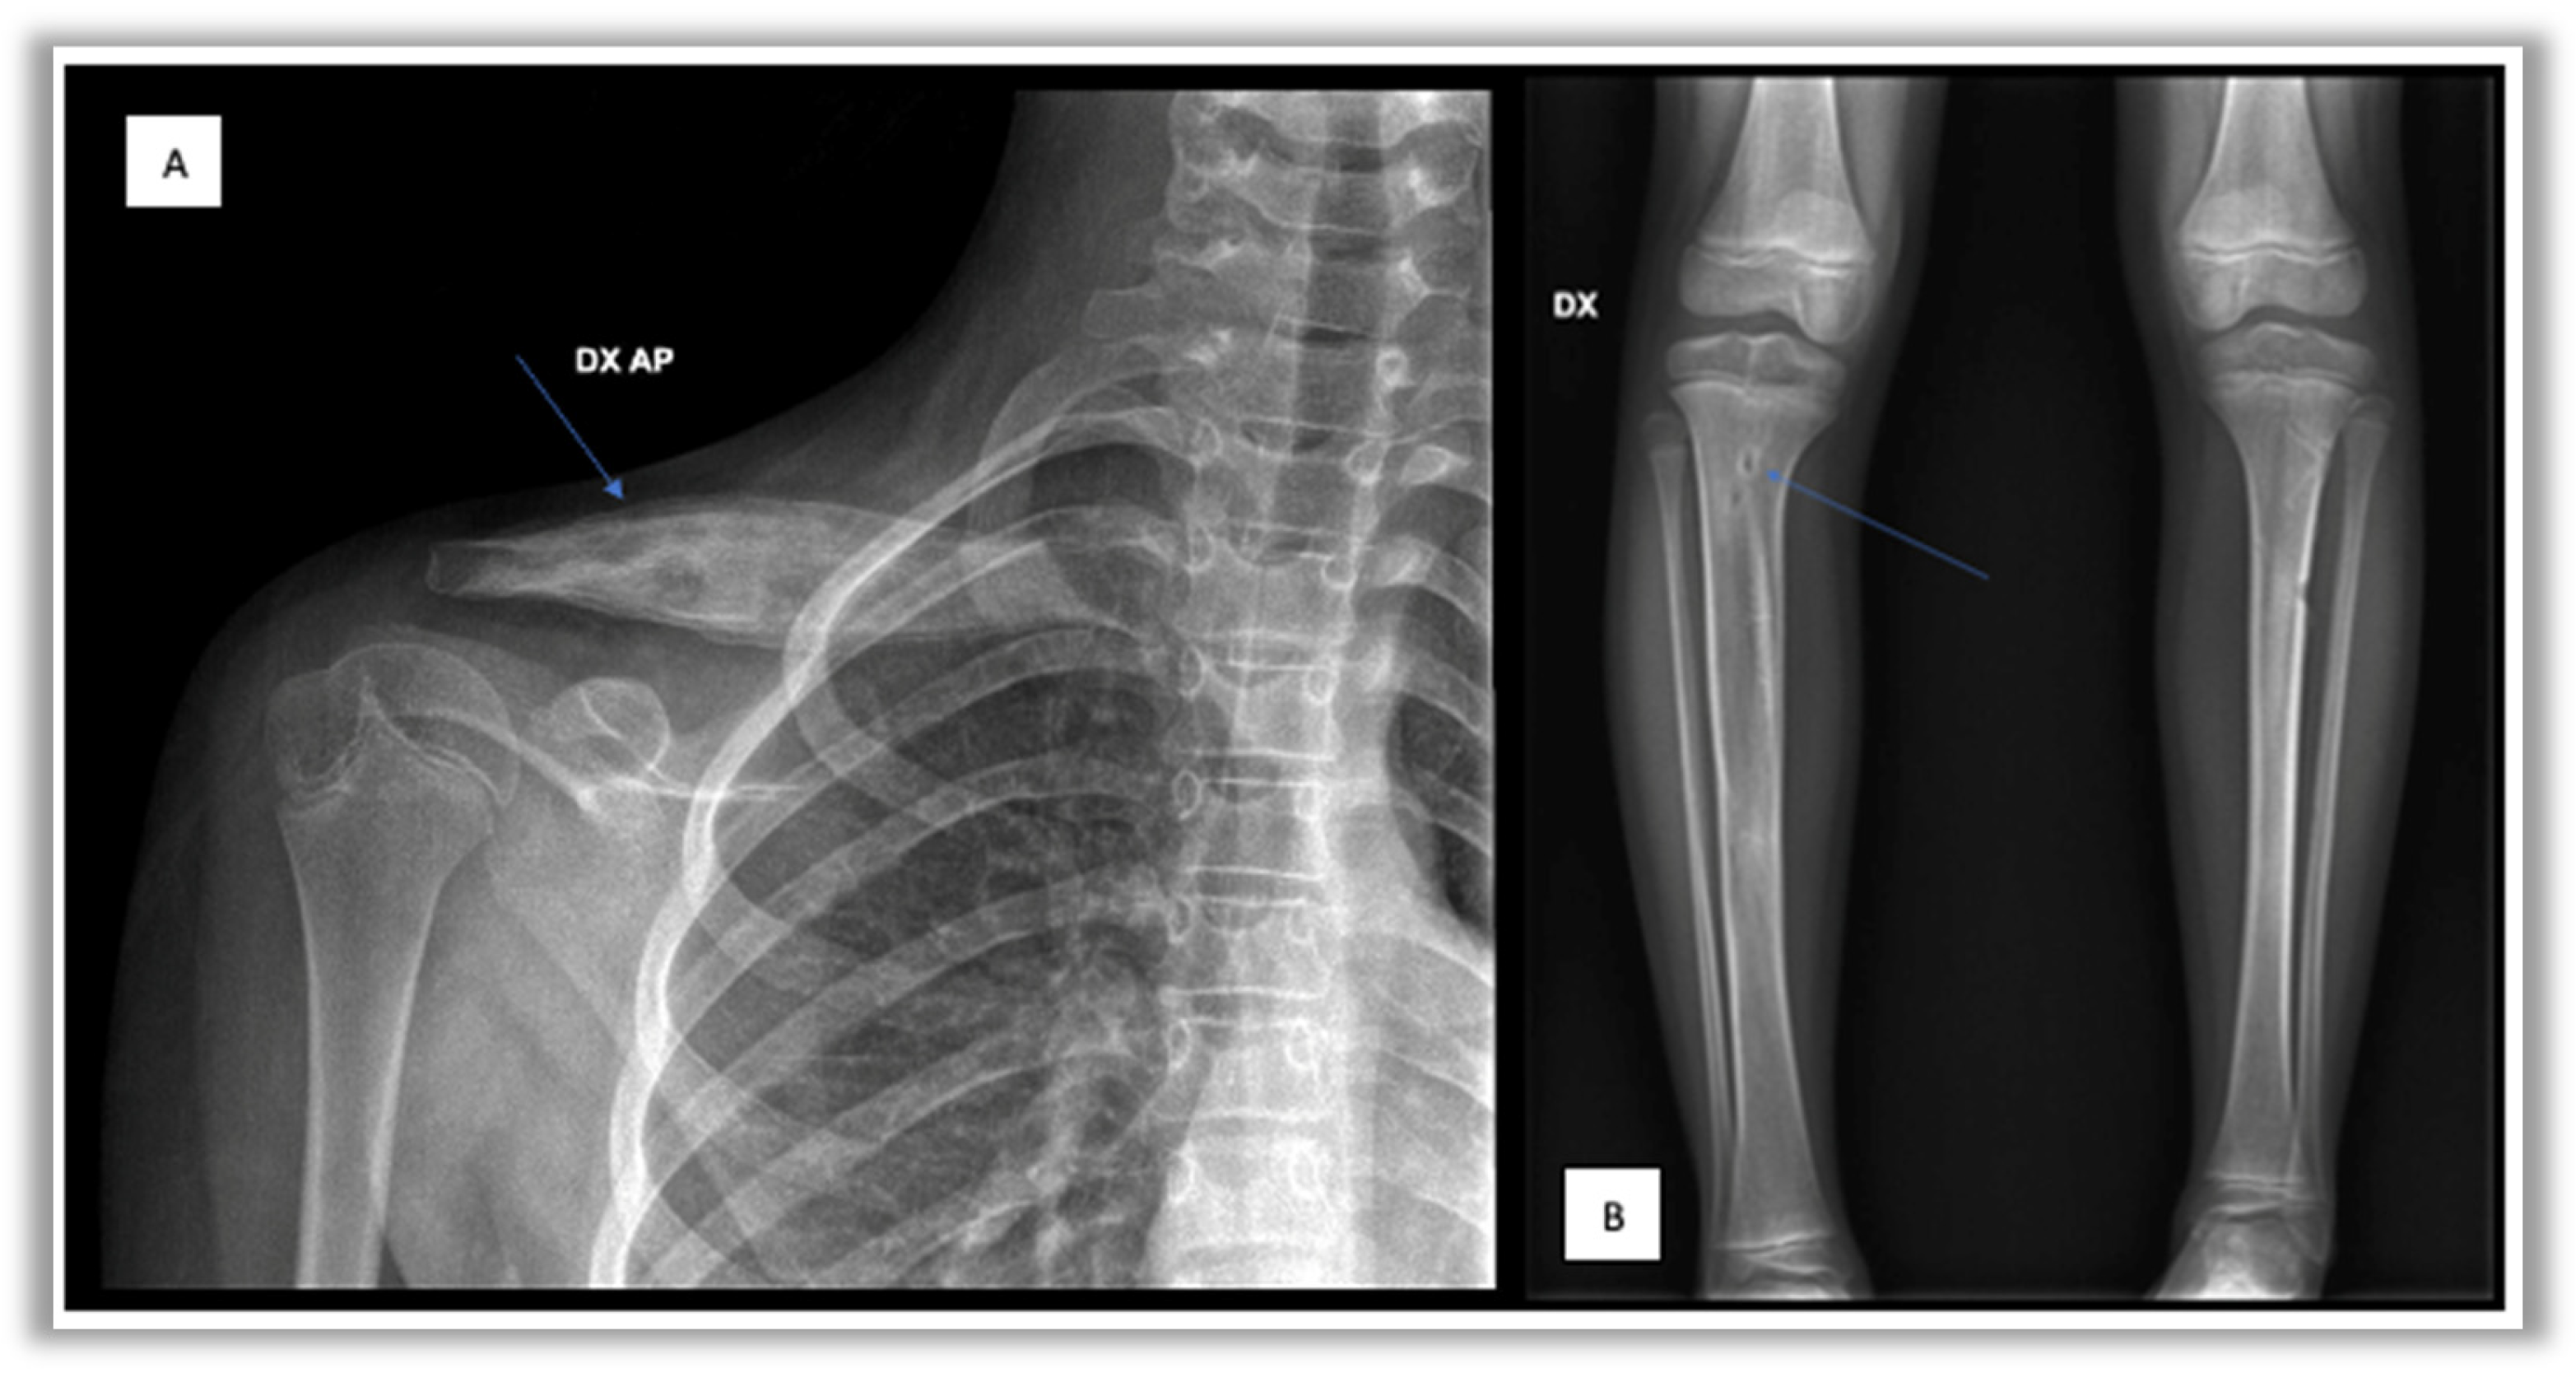

- Conventional radiography often represents the first-line investigation in patients with pain, but in the initial stages of the disease it is often negative. The first radiological changes are evident at the metaphyseal level near the growth cartilages, then an area of osteolysis surrounded by a sclerotic border can be highlighted in the evolution of the disease (Figure 1) [27].

Figure 1. Radiographic images. (A) Right clavicular lesion;(B) right tibial osteolytic lesion. - -